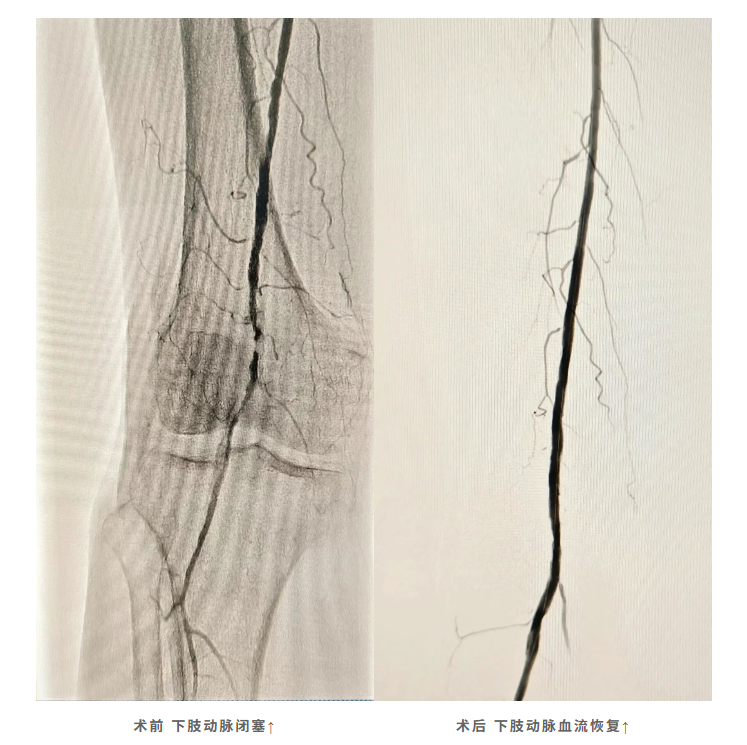

威远首例|技术突破护民生,我院成功实施首例下肢动脉闭塞介入治疗